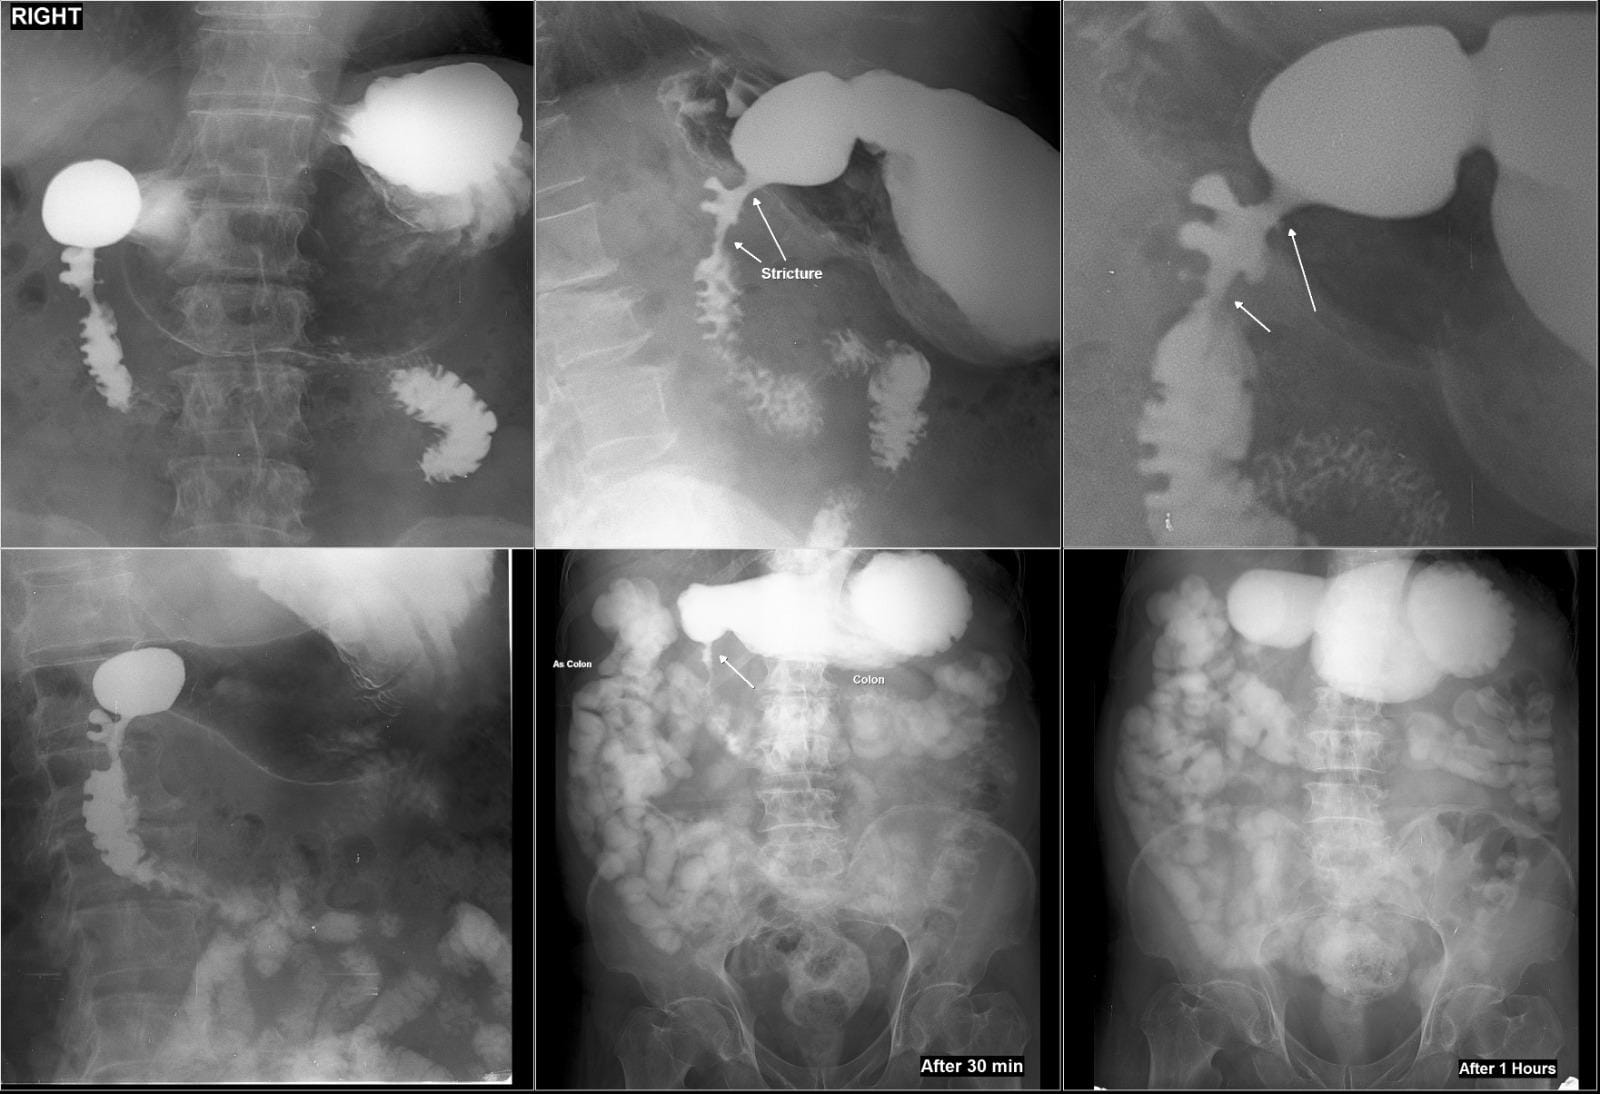

67/Male with symptoms of Gastric outlet obstruction (GOO) distension of stomach, vigurous peristalsis, hold up with stricture of D1- proximal D2

Radiological signs of a deformed duodenal bulb, often caused by chronic scarring from peptic ulcer disease, include a "cloverleaf" appearance (due to multiple pseudodiverticula and spasm), persistent irregularity, and base line tenting. Other signs include ulcer craters, narrowing, and, in severe cases, strictures or "pseudodiverticulum" formation.